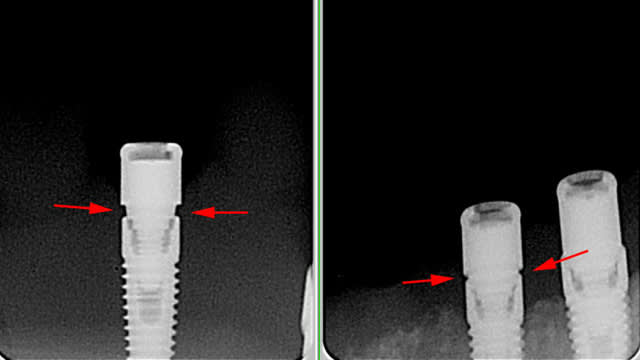

2009 : Sur un cas de locator sur un implant SD le pilier locator ne se visse pas à fond il reste un hiatus entre l'implant et le pilier)... VOIR FICHIER JOINT locator_test.jpg.

Cela remonte au directeur France de l'époque qui pense d'abord que l'ai abîmé le pas de vis de l'implant, mais comme on obtient la même chose sur des répliques d'implants, il avoue finalement que les ingénieurs Keystone ont fait un mauvais design du pilier (il aurait fallu un biseau qui n'a pas été fait)... il m'a même adressé le schéma du pilier avec en rouge ce qui aurait dû être fait ... VOIR FICHIER JOINT Locator prima SD Gap.pdf.

Pour tes locators, tu n'as pas peur que ça pète? Parce que le filetage de la vis encaisse toute les forces là, ça pues la fracture

et ton courrier officiel ne vaut rien, un expert dira que ça a pété car c'était pas à fond et que c'est ta responsabilité de ne pas le poser

Oui, j'ai un peu peur.... mais l'implant était posé et ce n'est qu'au moment de mettre en place le pilier locator que l'on a constaté le problème...

Donc à part une dépose sur une crête déjà un peu fine....

ouaip...à mon avis j'ai tout bon...

le genesis à une plateforme 3.8mm, les références pour les locators c'est G71500 et suivant

le prima c'est un 3.5mm et les références (si c'est bien des 3 ou 4mm de haut) devraient être du type 45259K ou 45260K

du coup si tu essayes de visser un locator de 0.3mm trop large...et bien çà de donne çà...

vérifie les références de tes piliers mais amha çà doit être çà (ou alors Zeist c'est planté dans les piliers livrés...)

1) Le pilier locator a été réalisé par ZEST à partir des plans fournis par Keytone... C'est Keystone qui a fait une erreur. Le directeur de l'époque l'a reconnu (il a envoyé les plans avec en rouge le biseau qui aurait dû être réalisé). Point final.

Dire que le problème est résolu depuis 2006 est vraiment d'une mauvaise foi absolue. Le gap existe, le problème a été constaté, mais Keystone plutôt que dépenser de l'argent (jeter les pièces défectueuses et en fabriquer des nouvelles)a déclaré que cette situation ANORMALE était NORMALE...